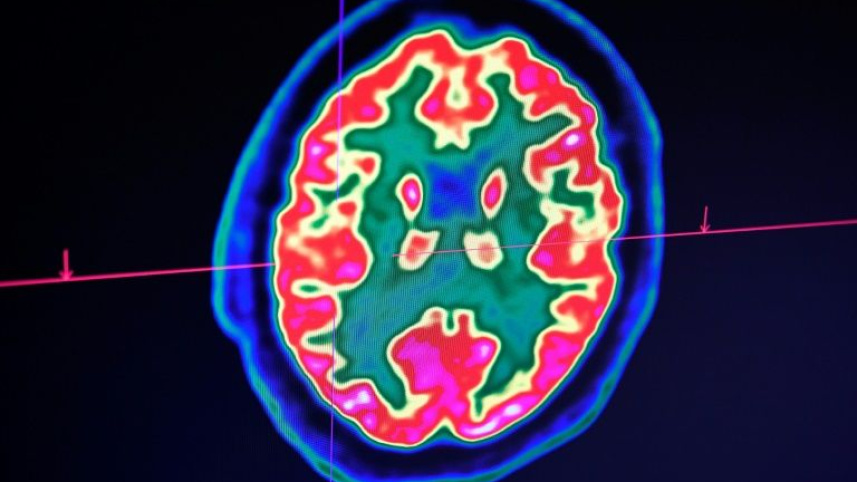

A paper in the New England Journal of Medicine this week examining 58 patients in Strasbourg, France found that more than half were confused or agitated, with brain imaging suggesting inflammation.

Her team is documenting striking cases including seizures in Covid-19 patients with no prior history of the episodes, and "unique" new patterns of tiny brain hemorrhages.

One startling finding concerns the case of a man in his fifties whose white matter -- the parts of the brain that connect brain cells to each other -- was so severely damaged it "would basically render him in a state of profound brain damage," she said.

Brain imaging and spinal taps are difficult to perform on patients on ventilators, and since most die, the full extent of neurologic injury isn't yet known.